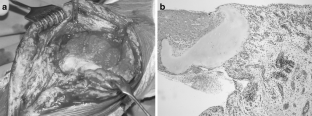

The diagnosis of Charcot arthropathy in the knee is rare. However, there is an increasing number of diabetic patients, and they are living longer due to improvements in treatment. Because neuropathic arthropathy is a late effect of peripheral neuropathy, we can expect an increasing incidence of neuropathic arthropathy. Total knee arthroplasty is the preferred choice of treatment by patients, although it may also be associated with a high incidence of serious complications. This case report presents a young female with diabetes mellitus and Charcot arthropathy of the knee managed by total knee arthroplasty and a literature review. The report encompasses a 5-year follow-up of the patient, from the first contact after knee distortion through diagnosis of Charcot arthropathy and the performance of total knee arthroplasty with outpatient controls. The diagnosis was established on the basis of the rapid destruction of the medial tibial condyle after knee distortion in a patient with neuropathy. Neuropathic arthropathy was confirmed by histology. The patient refused knee fusion and total knee arthroplasty was performed. The patient quickly achieved a painless, stable knee with a 130-degree range of motion. However, a radiolucent line appeared under the tibial component due to premature weight-bearing. The patient was ordered to refrain from weight-bearing for the next 3 months, and the knee was healed. While the management of Charcot arthropathy in the knee remains controversial, total knee arthroplasty is not a contraindication. Early diagnosis, appropriate choice of implant and operative technique, and long-term weight protection are essential.

Fig. 1